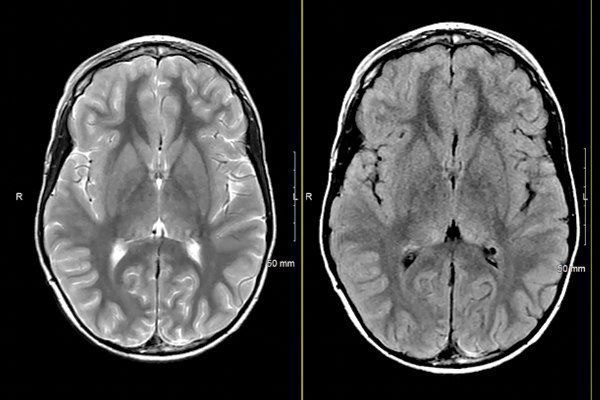

MRIOnline Mastery Series: Neurofibromatosis Type 1 (NF1) 2021 is a specialized digital course focused on the imaging assessment of neurofibromatosis type 1 and its pediatric manifestations. This series provides detailed guidance on identifying key anatomical features, interpreting advanced imaging findings, and understanding the clinical significance of various presentations in NF1.

This course offers a comprehensive review of neurocutaneous syndromes with emphasis on NF1, covering a wide range of imaging cases and clinical scenarios relevant to pediatric patients.

MRIOnline Mastery Series: Neurofibromatosis Type 1 (NF1) 2021 addresses critical aspects of NF1 imaging, strengthening expertise in the interpretation of complex neurocutaneous syndromes within pediatric radiology. Understanding the diverse presentations of NF1 supports informed diagnosis and effective communication in clinical practice.